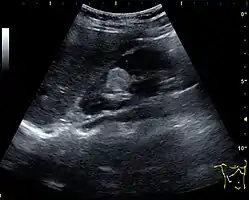

Masses are seen as a distortion of the normal renal architecture. Most renal masses are simple cortical renal cysts with a round appearance and a smooth thin capsule encompassing anechoic fluid. The incidence increases with age, as at least 50% of people above the age of 50 have a simple cyst in one of the kidneys. Cysts cause posterior enhancement as a consequence of reduced attenuation of the ultrasound within the cyst fluid (Figure 5). The simple cyst is a benign lesion, which does not require further evaluation.[1]

Figure 5. Simple renal cyst with posterior enhancement in an adult kidney. Measurement of kidney length on the US image is illustrated by '+' and a dashed line.[1]